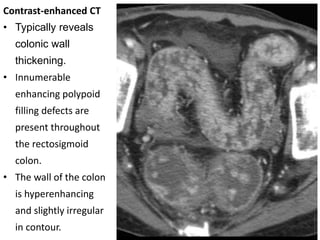

Contrast-enhanced CT

• Typically reveals

colonic wall

thickening.

• Innumerable

enhancing polypoid

filling defects are

present throughout

the rectosigmoid

colon.

• The wall of the colon

is hyperenhancing

and slightly irregular

in contour.